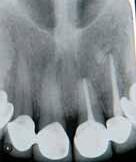

A 19 year old girl was referred to Endodontic Department of Jahra Dental Speciality Centre for root canal treatment of lower right first mandibular molar. Pulpotomy of the tooth had already been carried out. On examination the tooth was asymptomatic and medical history was non contributory. Radiograph revealed two separate roots. (Figure 9). Endodontic procedure was carried out under local anesthesia and rubber dam isolation. Access opening showed four canal orifices, two mesially and two distally. The orifices of mesial canals were placed slightly apart and after initial debridement, the orifices appeared unclean. Further exploration revealed a third orifice located more towards the mesiolingual canal. Working length radiograph with a distal angulation presented with three separate canals in mesial root and two in distal root. (Figure 10). Working length of all the five canals were determined followed by biomechanical preparation and obturation. (Figure 11). After one week the tooth was restored with permanent restoration and patient was followed up.

Figure 9- Pre operative radiograph.Figure 10- Working length radiograph showing three mesial and two distal canals.

Figure 11- Post obturation radiograph showing five canals.